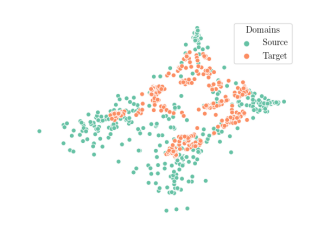

We compare the -distance of categorical features and domain features. Fig. 5 (a) shows that domain difference is higher in domain features than in categorical features. This indicates that domain features contain more domain information whereas categorical features are more domain-invariant. Fig. 6 shows the t-SNE plot of categorical features in both domains for MIDNet. From Fig. 6 (a), we observe that the categorical features learned by MIDNet enable the anatomical classification. Fig. 6 (b) shows that the learned categorical features are domain-invariant.

In addition, we utilize t-SNE plots for feature visualization in Fig. 10. Comparing Fig. 10 (a) and Fig. 10 (b), we observe that with mutual information disentanglement, (1) samples from the same category are more tightly clustered (see the top row) and (2) the source domain and the target domain are overlap more (see the bottom row). This indicates that mutual information disentanglement is important for learning categorical-focused and domain-invariant features. Fig. 10 (a), (c)-(d) show that the proposed method outperforms other state-of-the-art methods for learning category-discriminative and domain-invariant features, especially for unseen categories in the target domain (e.g., (a) vs. (d)).